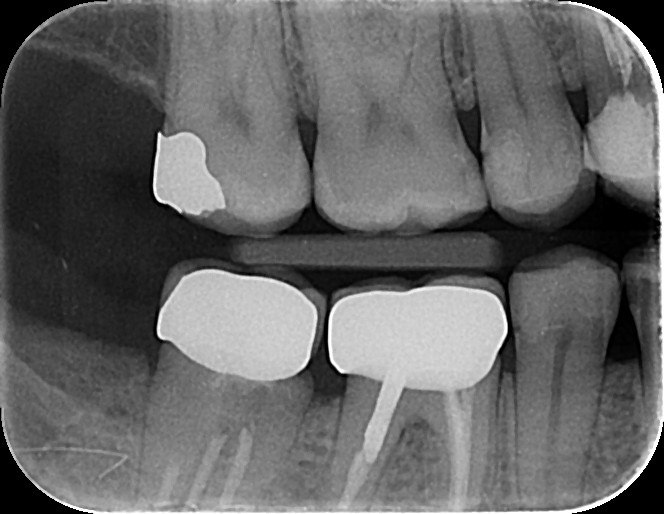

1. Which surfaces shows dental caries?

2. Which surface needs restoration?

4. Which surface needs restoration?

5. Which surface needs restoration?

8. Which surface needs restoration?

14. Which surfaces shows recurrent caries?

15. Which surface shows recurrent caries?

18. Which surfaces need restoration?

32. Which surfaces needs restoration?

38. Which surfaces shows recurrent caries?

40. Which surfaces shows recurrent caries?

42. Which surfaces shows recurrent caries?

43. Which surface shows recurrent caries?

45. Which surface shows recurrent caries?

46. Which teeth shows recurrent caries?

47. Which surface(s) shows recurrent caries?

50. Which surface(s) shows recurrent caries?